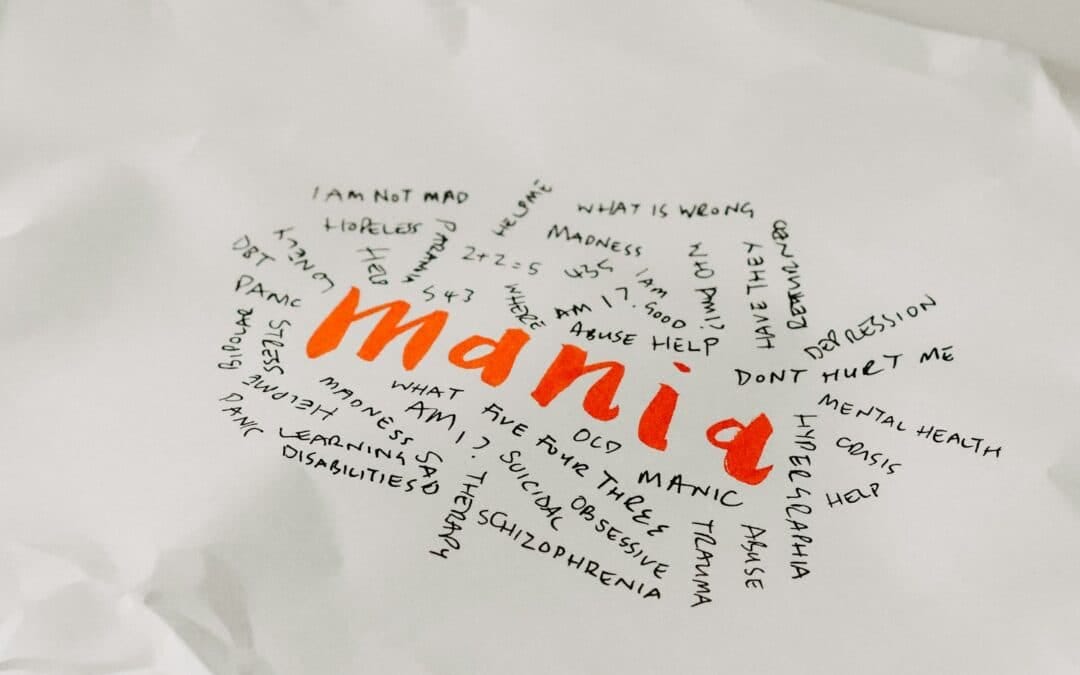

Schizophrenia Schizophrenia is a complicated mental health condition that is often related to psychosis. There’s lots of misconceptions about it, the illness is still very much misunderstood and has a lot of stigmas attached to it. However, 1 in every 100 people...